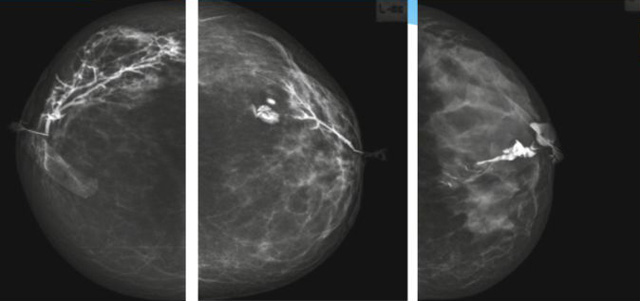

乳腺導(dǎo)管內(nèi)乳頭狀瘤分為以下兩個,位于乳暈區(qū)大導(dǎo)管的中央型乳頭狀瘤,起源于末梢導(dǎo)管小葉單位的外周型乳頭狀瘤。外周型乳頭狀瘤常常沒有明顯的的臨床表現(xiàn),常因X線或乳腺超聲設(shè)備檢查發(fā)現(xiàn)。重點要關(guān)注的是中央型乳頭狀瘤,發(fā)生于任何年齡的女性,以40~50歲者居多。它表現(xiàn)為:單側(cè)乳頭溢液,特別是血性溢液少數(shù)病人可在乳暈區(qū)觸及腫塊。從病理學(xué)上面講表現(xiàn)為導(dǎo)管上皮和間質(zhì)增生形成有纖維脈管束的乳頭狀結(jié)構(gòu)。這是它一個病理學(xué)上的表現(xiàn)。它的超聲表現(xiàn)為:病變導(dǎo)管囊狀擴張呈無回聲,內(nèi)可見乳頭狀低回聲或中等回聲。乳暈處的導(dǎo)管擴張,管腔內(nèi)可見邊界清楚的,低回聲實性結(jié)節(jié)。外周型導(dǎo)管內(nèi)乳頭狀瘤可,表現(xiàn)擴張為為低回聲的實性結(jié)節(jié),CDFI:部分腫瘤可顯示為軸心性的看到血流信號。乳腺增生癥:可見導(dǎo)管擴張,內(nèi)無乳頭狀實性回聲,導(dǎo)管內(nèi)乳頭狀癌:囊內(nèi)乳頭狀癌病變較大,不規(guī)則,厚基底,血流豐富。以囊性為主的混合回聲,形態(tài)不規(guī)則,內(nèi)見實性低回聲實性低回聲可見少量血流,病理為囊內(nèi)乳頭狀癌。

乳腺超聲設(shè)備檢查的價值在哪里呢?它可以檢查發(fā)現(xiàn)乳暈周圍的各種病變,對于單側(cè)乳頭溢液、血性溢液的患者,超聲是首選的影像學(xué)檢查方法。注意:導(dǎo)管內(nèi)乳頭狀瘤可合并不典型增生或,導(dǎo)管內(nèi)乳頭狀癌,手術(shù)前懷疑時候,就應(yīng)該手術(shù)切除而不是用微創(chuàng)手術(shù)。